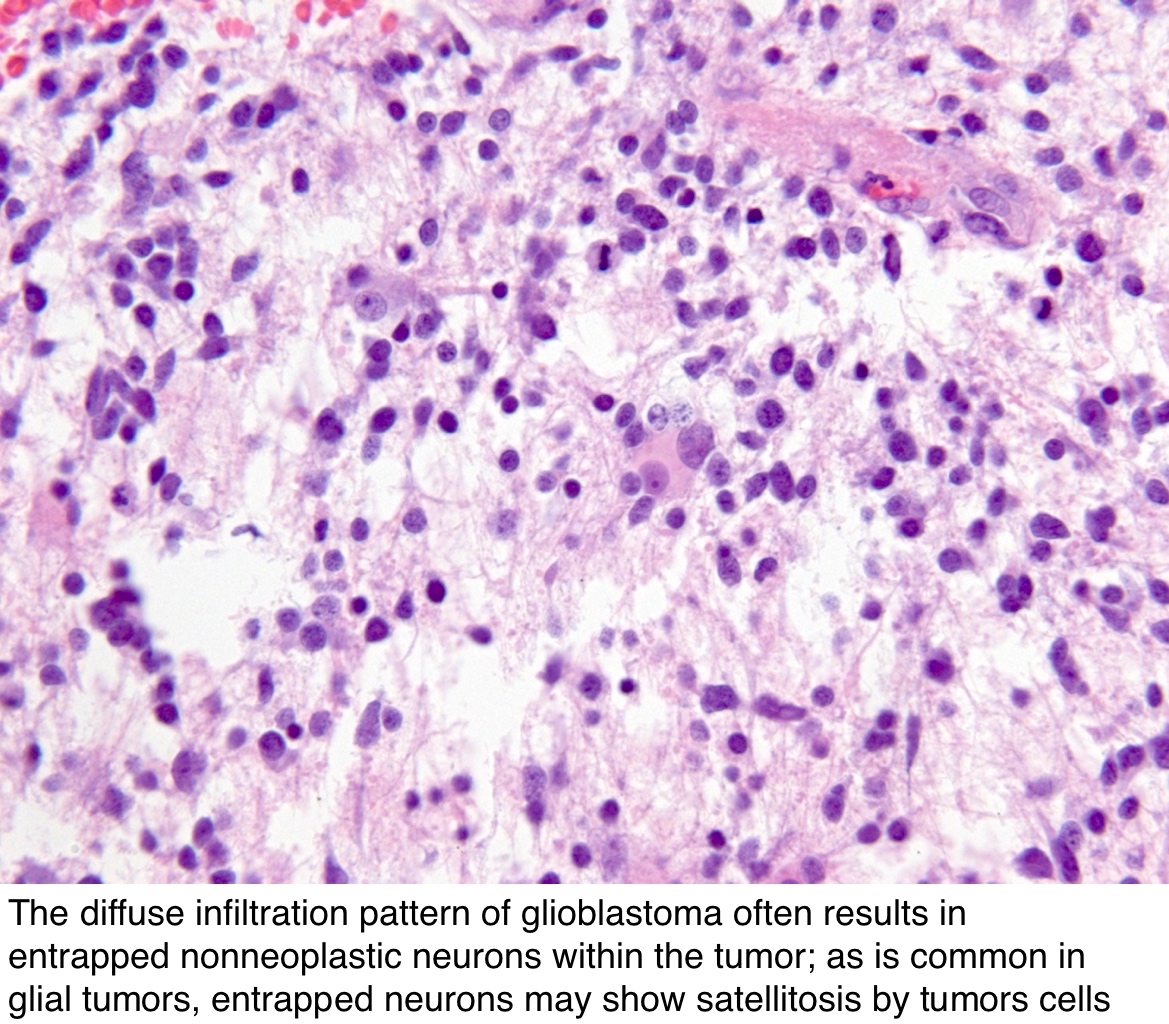

Микрофотографии гистологии глиобластомы головного мозга